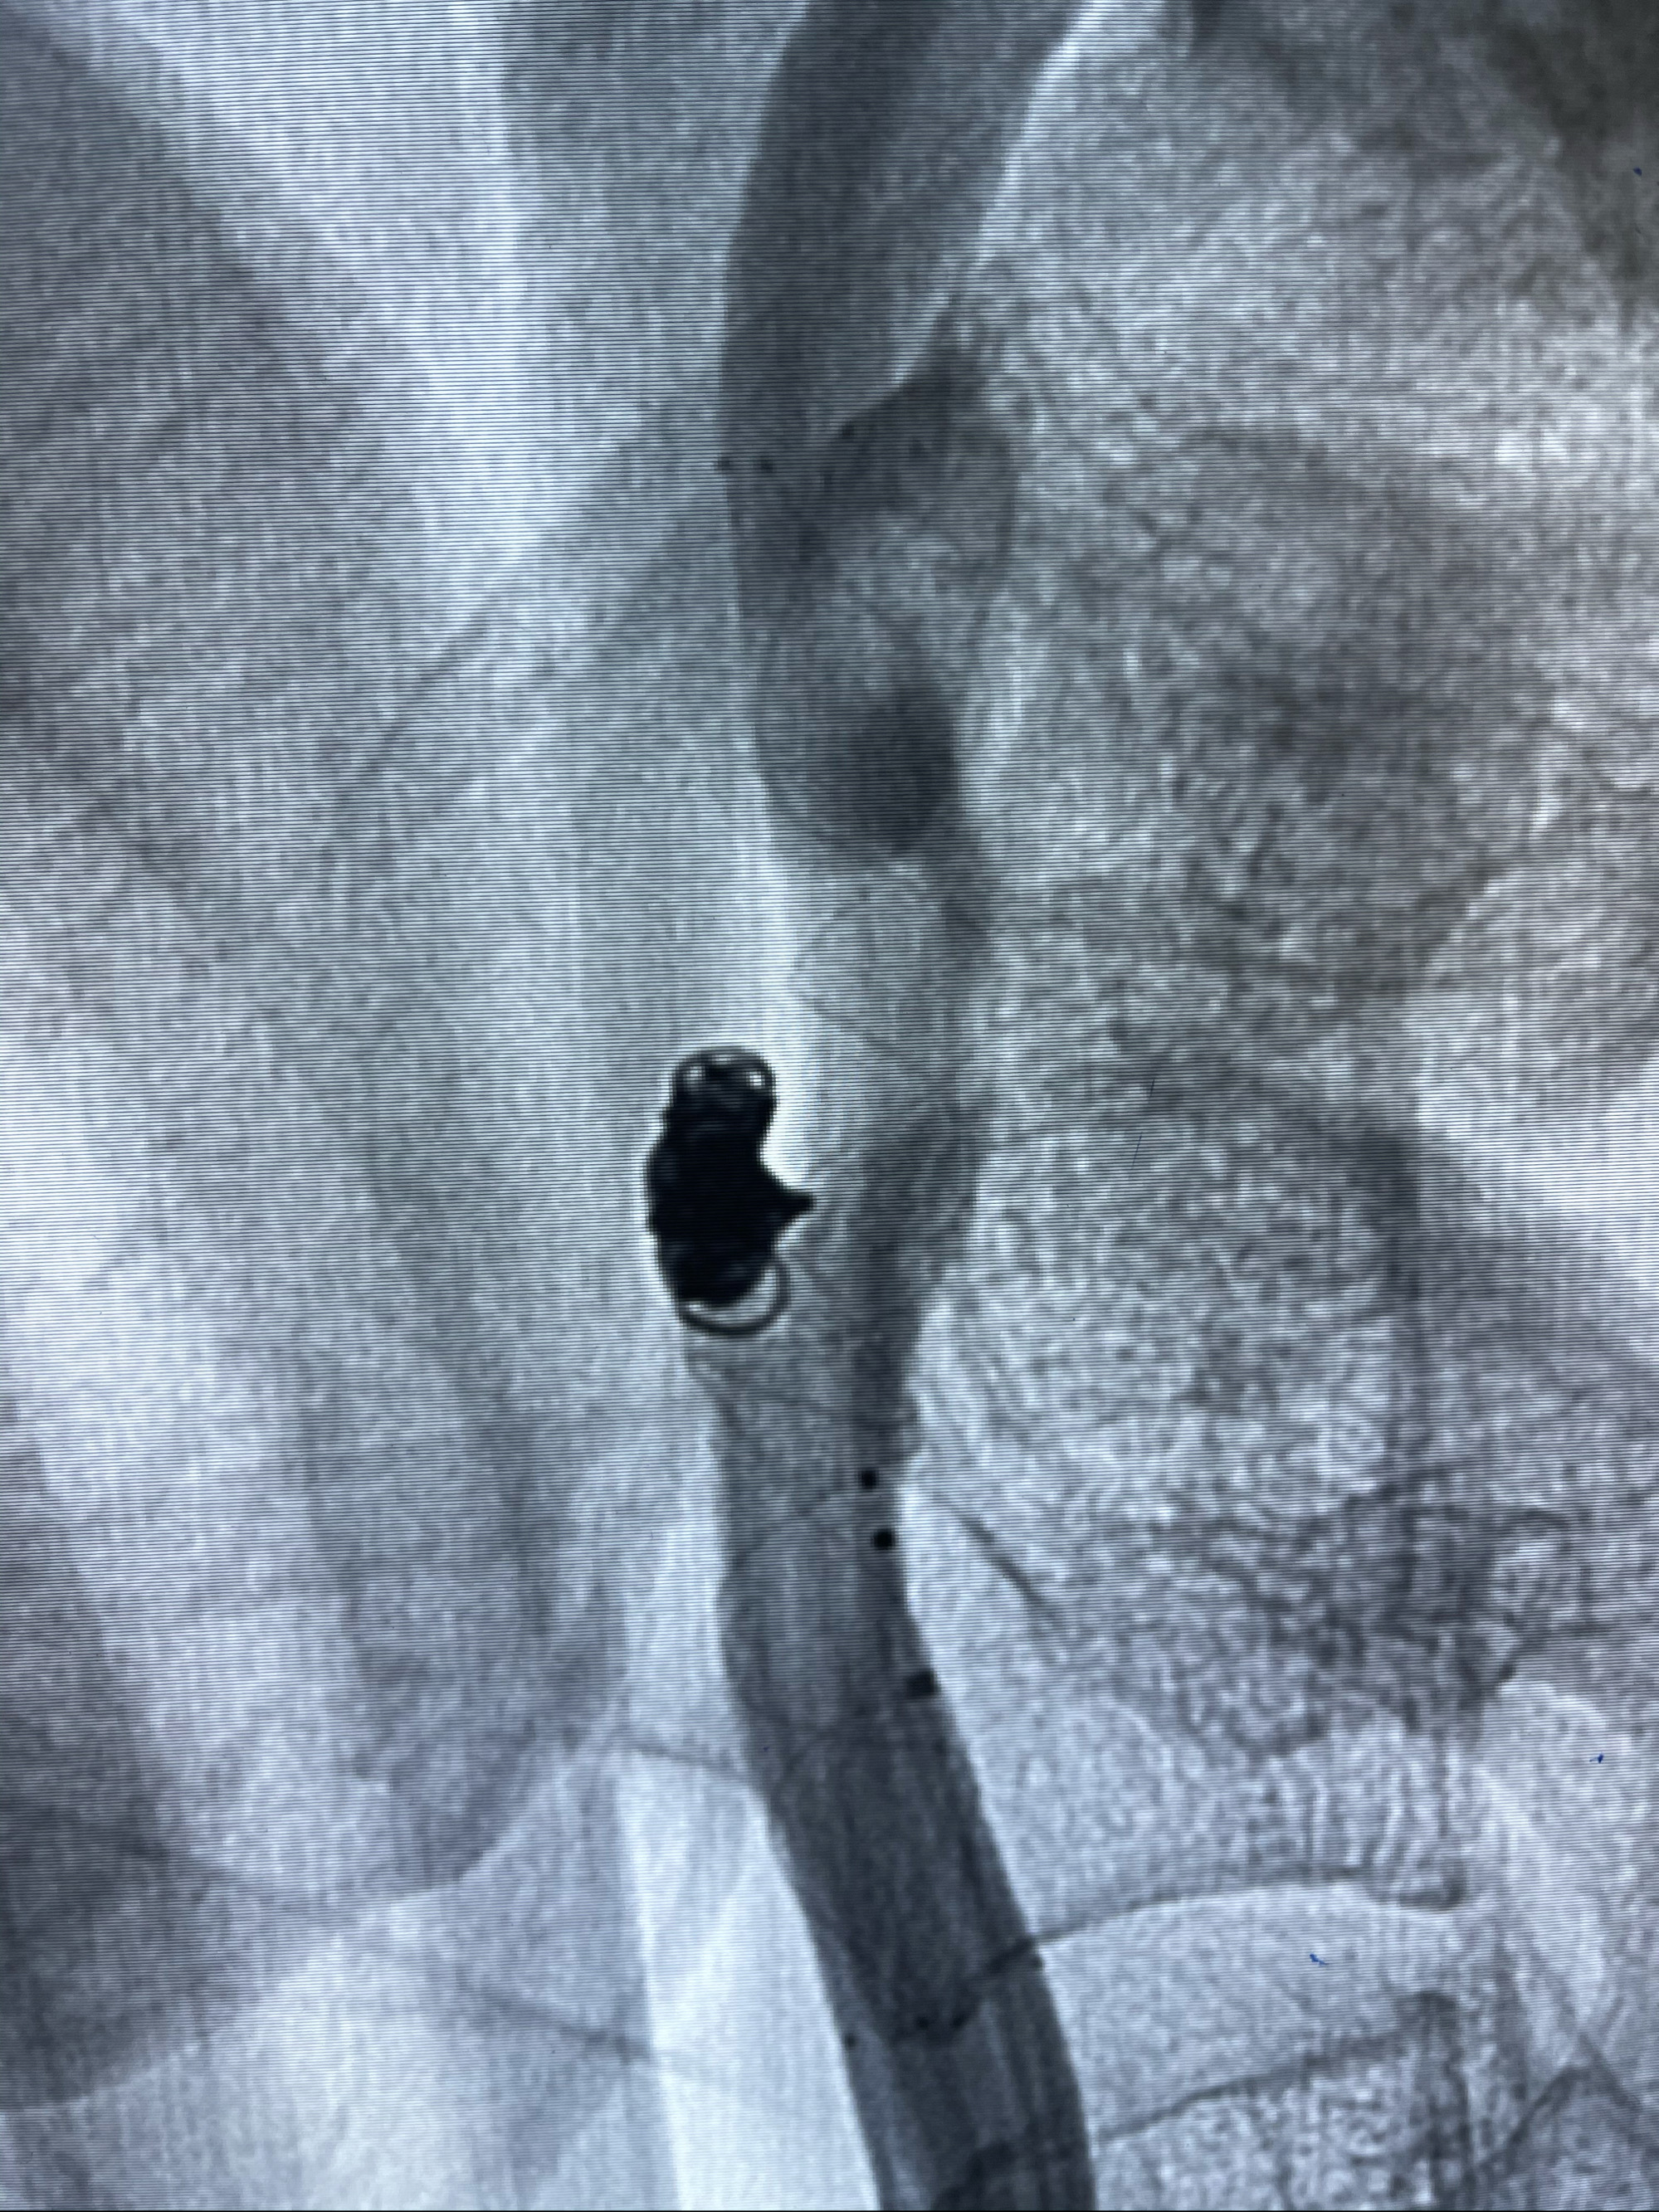

Echelon10 45°角微导管塑形后到位

8mm-40cm微弹簧圈成篮